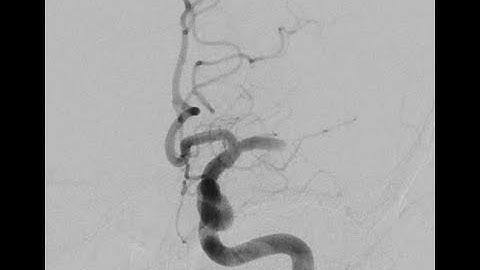

Stroke - Right M1 occlusion- Puncture to closure (1x)